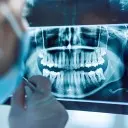

W tym wydaniu m.in: polerowanie i wygładzanie szkliwa i kompozytu, zasady wypisywania recept stomatologicznych, leczenie endodontyczne zębów stałych z niezakończonym rozwojem korzeni, rozwiązania w leczeniu rotacji zębów.